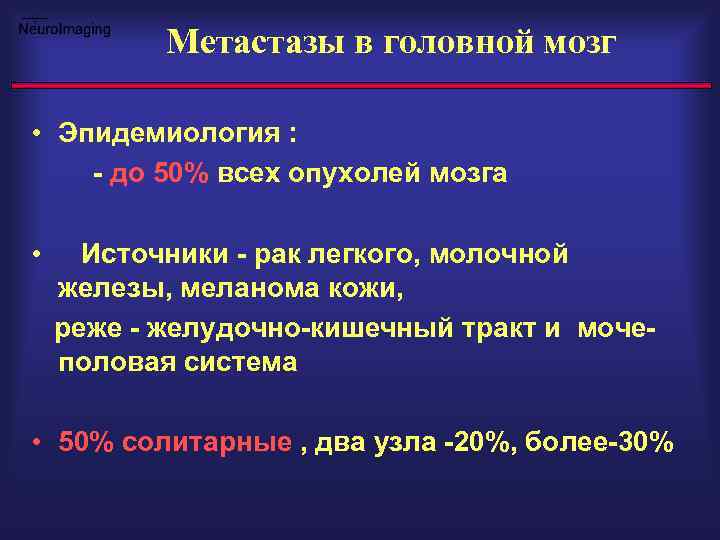

Метастазы в головной мозг • Эпидемиология : - до 50% всех опухолей мозга • Источники - рак легкого, молочной железы, меланома кожи, реже - желудочно-кишечный тракт и мочеполовая система • 50% солитарные , два узла -20%, более-30%